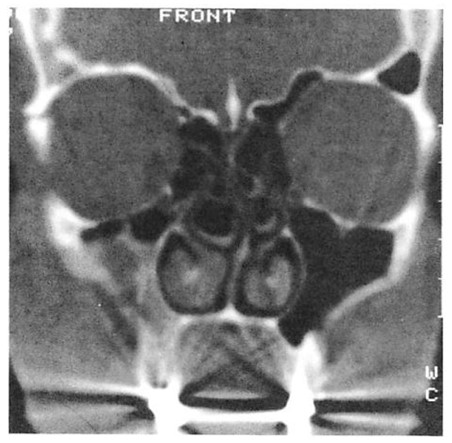

Fig 4. Highly comminuted fracture of supraorbital portion of large frontal sinus that extends to lateral orbit treated with open reduction and microplate and screw fixation. (A) Preoperative axial computed tomographic (CT) scan. (B) Postoperative axial CT shows stable reduction 2 months after injury. Note symmetrical contour of frontal soft tissues.

Fig 4. Highly comminuted fracture of supraorbital portion of large frontal sinus that extends to lateral orbit treated with open reduction and microplate and screw fixation. (A) Preoperative axial computed tomographic (CT) scan. (B) Postoperative axial CT shows stable reduction 2 months after injury. Note symmetrical contour of frontal soft tissues.